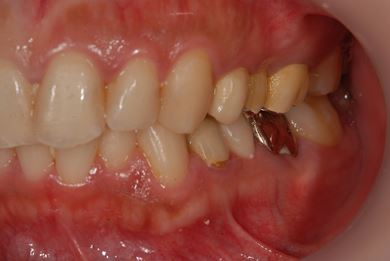

| 性別/年齢 | 女性 / 29歳 | ||||||||||||||||||||||||||||||||

| 治療方針 | 抜歯と同時にインプラント埋入を行い、治療期間を短縮する。 | ||||||||||||||||||||||||||||||||

| 治療内容 | インプラント2本(抜歯即日スピードインプラント)、ハイブリッドセラミッククラウン3本 | ||||||||||||||||||||||||||||||||

| 治療期間 | 8ヶ月 |